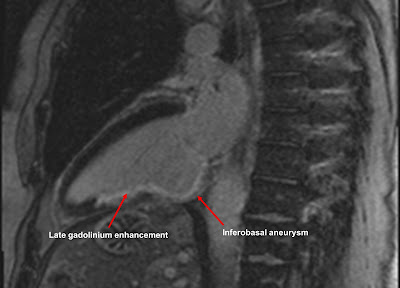

An example is shown above. This patient has had an inferior myocardial infarction in the past, caused by occlusion of their right coronary artery. We can see evidence of LGE in the inferior wall of the left ventricle, corresponding to the area of infarction. You'll also notice a bulge in the basal inferior wall, indicating an inferobasal aneurysm.

You'll see that the LGE is subendocardial rather than epicardial. This is because myocardium infarcts 'from the inside to the outside'. In other words, the subendocardium is always involved in an infarction, but the extent to which the infarction extends outwards varies from case to case. In some cases the LGE stays subendocardial, in others it can be 'full thickness'.